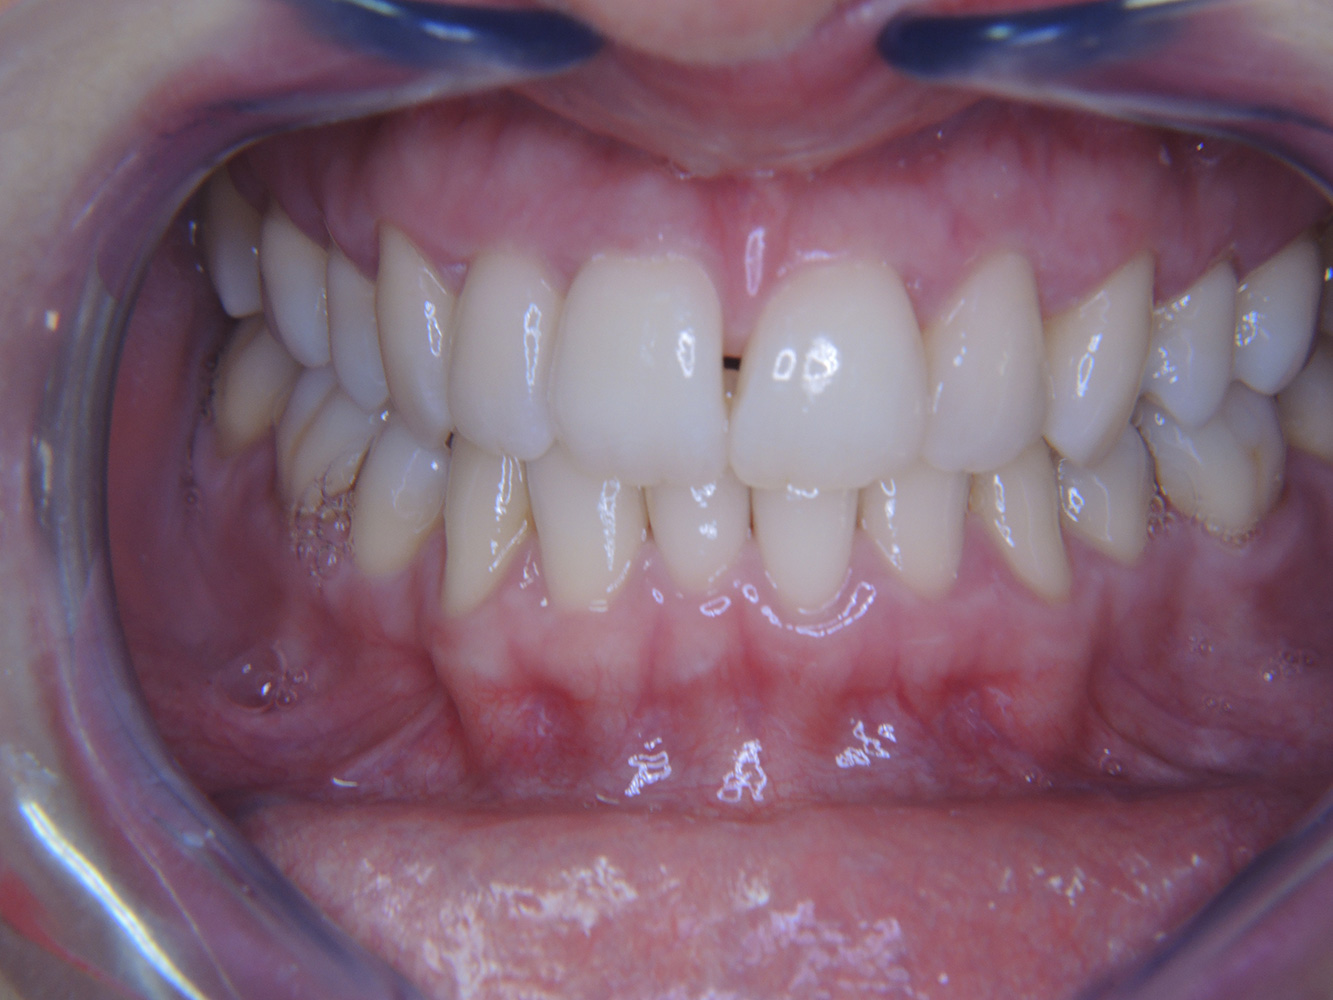

The diabetic patient with good oral health

A 51-year old diabetic patient presents with good oral health at a prevention session. Her blood sugar levels are stable at HbA1c = 6.2%, and thus her condition is thought to be sufficiently managed with the antidiabetic drug metformin. The patient has no existing restorations or early oral disease. Using the dental results, it is possible to determine gingivitis in spite of an otherwise stable condition. more

The (orally) healthy patient with implants

In the medical history, the 55-year-old patient states that he has no systemic disease and is not taking any medication. The patient’s lifestyle is similarly unremarkable. The patient has a few tooth restorations and two implants (2nd and 4th quadrants). On the basis of current findings, gingivitis is identified in an otherwise stable periodontal condition on the reduced periodontium (stage III, grade A). more